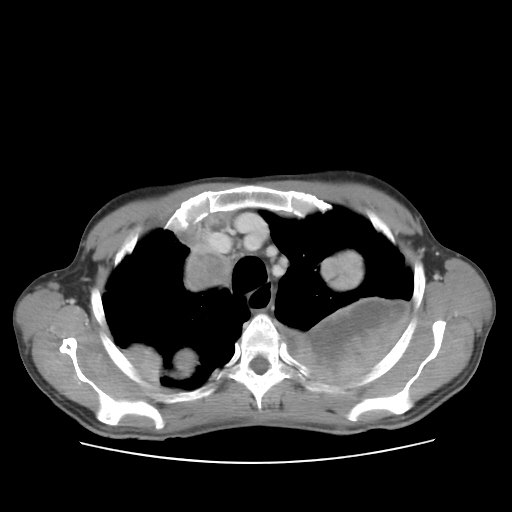

USG(Abdomen)... CECT chest

HRCT was done on 22 feb 2016